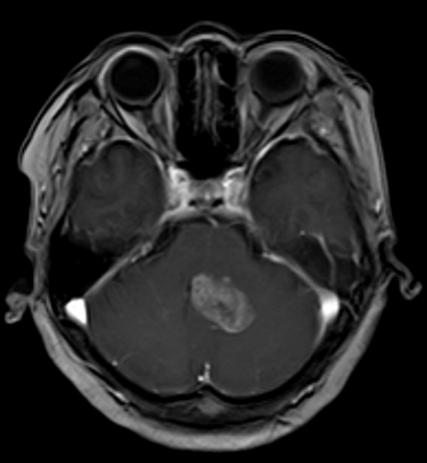

3. MRI检查:MRI在神经系统疾病的诊断中优势显著,对于脑肿瘤、脑梗死、脊髓病变等的诊断准确性较高。例如,对于一些早期的脑肿瘤,MRI能够更清晰地显示肿瘤的位置、大小、范围以及与周围组织的关系,有助于制定治疗方案。在关节疾病方面,MRI可以清晰地显示关节软骨、半月板、韧带等软组织的损伤情况,对于膝关节半月板损伤、交叉韧带断裂、肩关节肩袖损伤等疾病的诊断具有重要价值。此外,MRI在乳腺疾病、盆腔疾病等方面也有广泛的应用。

脑肿瘤T1WI+C、右膝外侧半月板撕裂、右侧膝前交叉韧带断裂、右侧肩袖损伤